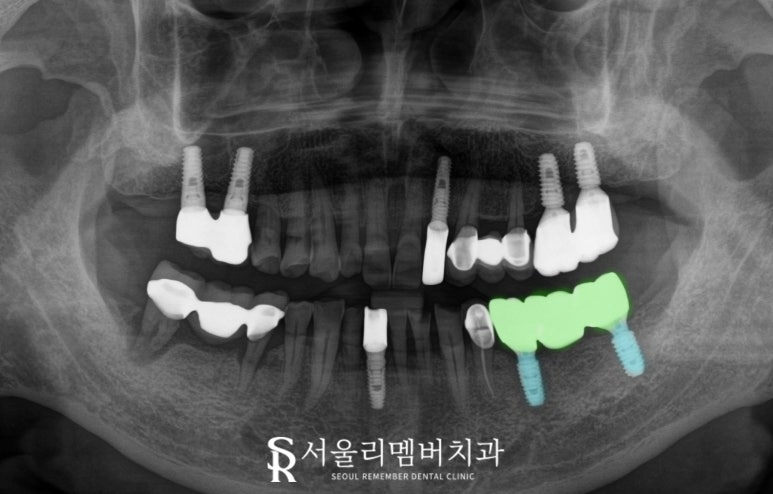

상도동 치과 에서는

비어있는 왼쪽 아래 어금니의

기능을 회복하기 위하여

디지털 임플란트를 하기로 했습니다.

ct와 구강 스캔을 활용하여

안전하고 정확한 위치에

수술할 수 있도록 하는 방법인데요,

디지털 가이드를 활용하여

픽스처의 식립 위치, 각도, 깊이, 방향 같은

모든 정보를 사전에 모의 시술해볼 수 있다 보니

그만큼 시술 시간도 줄어들고

안전성과 전문성도 높아진답니다.

불필요한 절개를 하지 않으니

출혈과 붓기도 적어

고령 또는 전신질환을 앓고 있어도

가능하다는 게 큰 장점입니다.

상도동 치과 에서 사전에 계획한 대로

수술이 잘 되었다면

이제는 보철을 올리게 되는데,

이 케이스에서는

고정력을 잘 얻을 수 있는 위치에

픽스처를 2개만 식립하고,

나중에 올려드릴 보철을

브릿지 타입으로 제작하여

3개의 치아 역할을 회복할 수 있도록

해드렸습니다.

2025.06.20

비용은 절감해 드리면서

구치부의 교합력은 나눠서 분배하여

제 역할을 모두 할 수 있도록 한 것이죠.

또한 지르코니아 소재라

심미성은 뛰어나고,

교합면에 있는 홀(HOLE)로

내부 나사를 조였다 풀었다 하며

유지관리를 할 수 있으니

환자는 정기검진만 잘 오시면 됩니다.